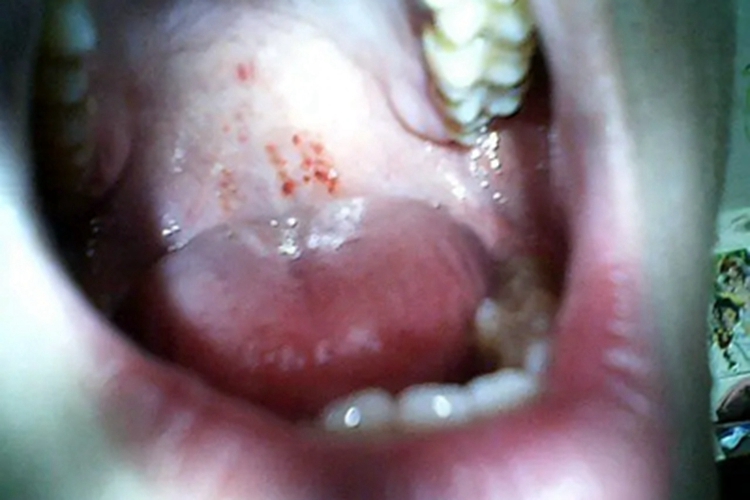

巨球蛋白血症性紫癜可表现为口腔黏膜出血,出现红色的血点,或是大小不一的红斑,分布不集中,数量不等,部分患者可伴有乏力、体重减轻、发热等症状。